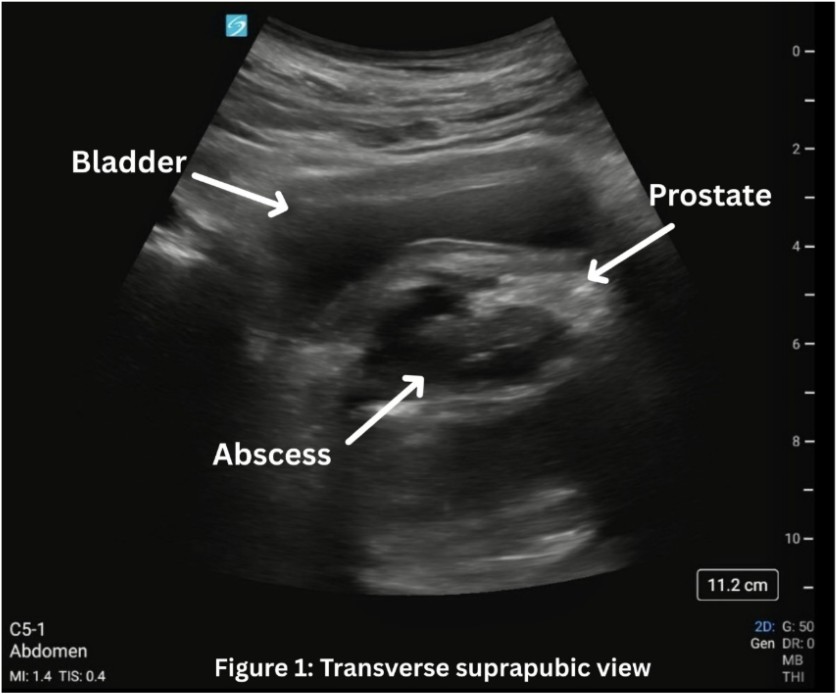

Our patient is a 42-year-old male with a medical history of insulin-dependent diabetes (IDDM), hyperlipidemia, and end-stage renal disease (ESRD) on dialysis who makes urine two times per week, who initially presented to the emergency department after having purulent penile discharge that started about twelve days prior, now with suprapubic abdominal pain and fullness for the past several days. He was afebrile and vital signs showed heart rate of 97 beats per minute, blood pressure of 79/57 mmHg, respiratory rate of 18 breaths per minute, and oxygenation of 97% on room air. On exam, the patient had suprapubic abdominal tenderness without peritoneal signs. Patient deferred rectal exam. On laboratory testing, the patient had a white blood cell count of 20.5K. Urinalysis showed greater than 100 white blood cells, 84 red blood cells, many bacteria, and was negative for nitrates. Due to concern for infection and possible sepsis, intravenous vancomycin and cefepime were initiated in the ED. Straight catheterization was initially attempted without any return of urine. Point of care bladder ultrasound was done to evaluate bladder volume for urinary retention. It revealed a hyperechoic mass extending into the bladder consistent with a large prostatic abscess (PA), though bladder volume was approximately 68 mL, and foley catheter was later placed. (Figure 1) A computed tomography (CT) scan of the abdomen and pelvis with intravenous contrast demonstrated multiple rim-enhancing fluid collections which measured collectively as 5.3 x 5 x 5.6 cm with fat stranding over the prostate. Urology was consulted, and the patient was admitted to the hospital. He underwent a transurethral unroofing of the PA with urology the next day, and urine and blood cultures grew Escherichia coli.

In our patient’s case, the use of point of care transabdominal ultrasound to investigate the patient’s sensation of urinary retention led to the preliminary diagnosis of PA. On ultrasound, in both the transverse (1) and longitudinal (2) view, a multiloculated abscess is seen, indicated by the hypoechoic areas, measuring approximately 5 x 5 x 5 cm. CT scan was then done to confirm and better characterize the abscess, urology was consulted, and ultimately the patient had definitive treatment with antibiotics and transurethral unroofing of the abscess in the operating room.

Figure 1: Transverse view of the bladder with prostate abscess.